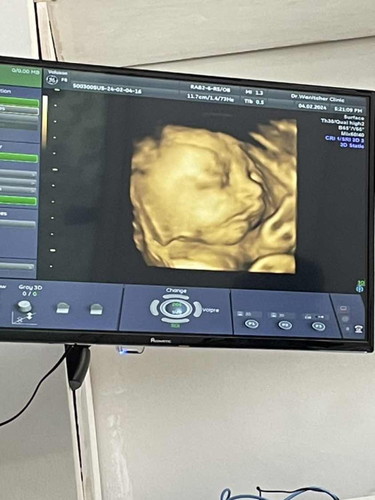

บ้านนี้ 25w น้ำหนักเด็ก 881 กรัม หมอบอกน้ำหนักกำลังดีเลยค่ะ 🥰

บ้านนี้ 27+ 3 วีค 1135 กรัมค่ะ🥰

ผู้ชายค่ะแม่ 🥰 ลงแต่ลูกเลย น้ำหนักแม่ไม่ค่อยขึ้นเยอะ🥰

จ้ำม่ำจังเลยลูก

ตอนออกอยากให้น้องพกแก้มออกมาด้วย🤣 ไม่ใช่ทิ้งไว้ในท้อง555